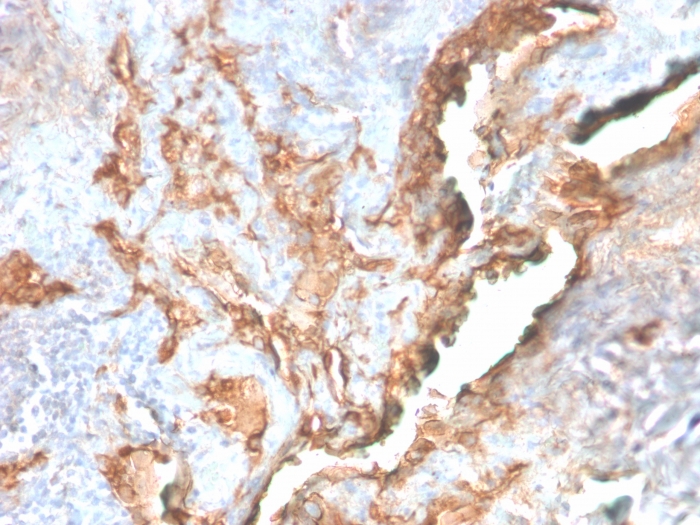

IHC-P analysis of human lung carcinoma section using GTX02725 Tenascin C antibody [TNC/2981R].